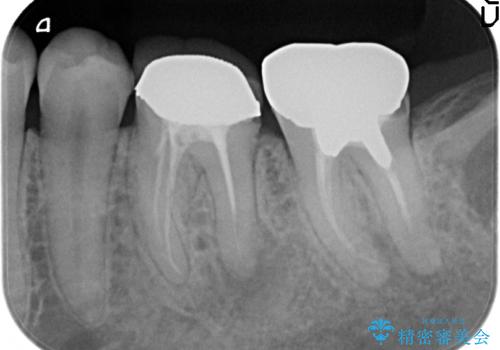

- 左下の奥歯でものを咬むと痛むので診て欲しいといらっしゃった方の症例です。

左下6、7番目の歯に根尖病変を認めたため、再根管治療後、オールセラミッククラウンによる補綴を行いました。